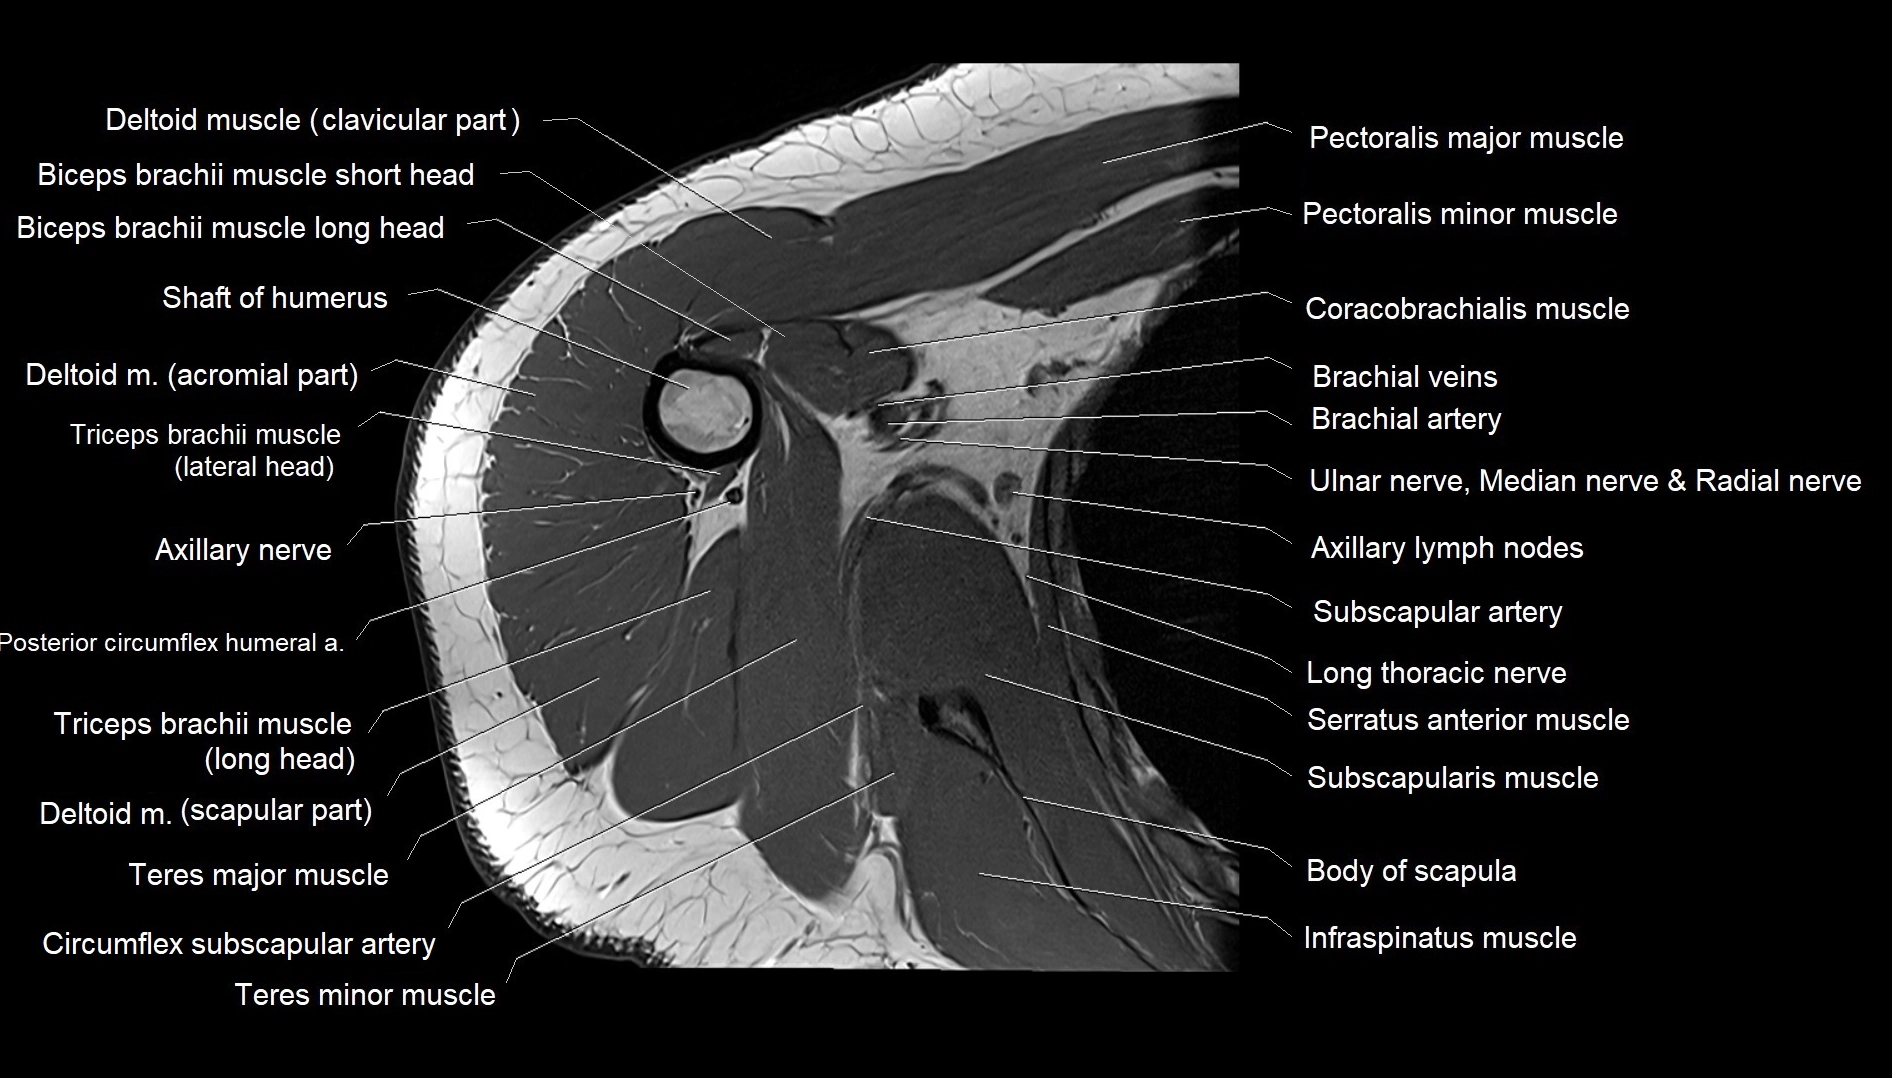

MRI images

image